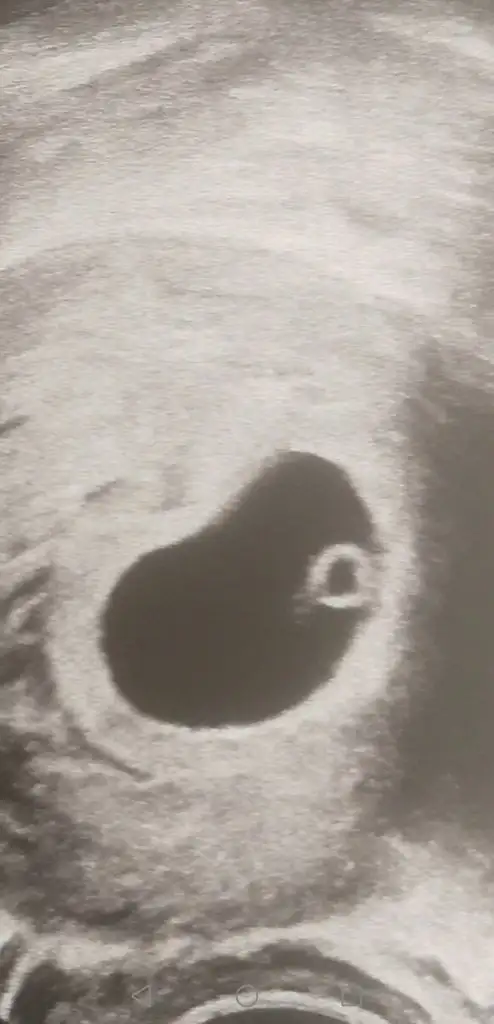

Amin inşallahSelamlar herkese. Rabbım gonlumuzdekini hepimize nasip etsin hayırlısıyla inşaallah. Bende uzun süredir takip ediyorum bugün 6+4le ilk ultrasona girdim 3 kızım var.

Böylede fotolar aldık teyzeleri. Tabiki gönlümde 3 kızdan sonra bide erkek evlat tatmak var ama böyle görünce insanın aklına cinsiyet hiç gelmiyor. Doktordan ciktim elime aldım anası kurban kız sanda oglansanda Bi güldüm kendi kendime